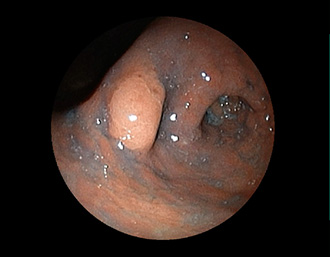

胃潰瘍(Stage S1)・・治療後5ヶ月

潰瘍の中心に白苔はなく、わずかに陥凹する潰瘍面に発赤が残る再生上皮が覆い尽くす(赤色瘢痕)。集中皺襞がなだらかに中心に延びている。→ ヘリコバクター・ピロリ感染を認めたため、除菌治療で駆除しました。

(通常画像)